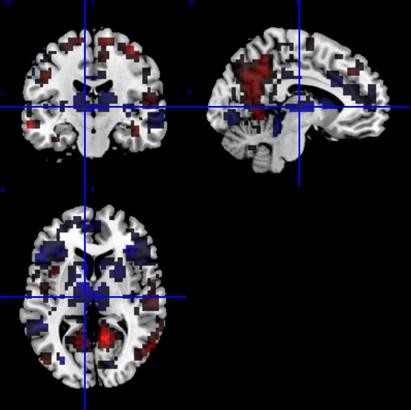

For classification of depressiona patients, we apply L1-regularized logistic regression of functional magnetic resonance imaging (fMRI) data. Our collabrators in Hiroshima Univeristy collected fMRI data in a semantic verbal fluency task of 20 severely depressed patients and 39 healthy controls. After processing of the data by SPM8, the Z-scores for each voxel were used for binary classification by logistic regression with L1-reguralized constraints, which is referred to as Least Absolute Shrinkage and Selection Operator (LASSO).

The algorithm achieved good classification performance (specificity: 83.0%, sensitivity 87.5% and F-score: 86.0% in 10-fold cross-validation), where the main contributing brain areas were left precuneus, superior and mid temporal lobe, left Thalamus and left superior parietal area (Fig. 1).

Figure 1: Brain areas mainly contributing to depression-control classification. They are identified by the logistic regression analysis with LASSO.